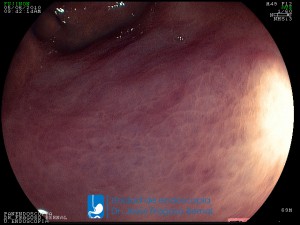

La Unidad de Endoscopía fue creada en 2002 por el Dr. Jesús Fragoso Bernal, es pionera en el estado por la utilización de la tecnología más avanzada, que nos permite ofrecer servicios integrales de diagnóstico y tratamiento para las enfermedades del aparato digestivo.